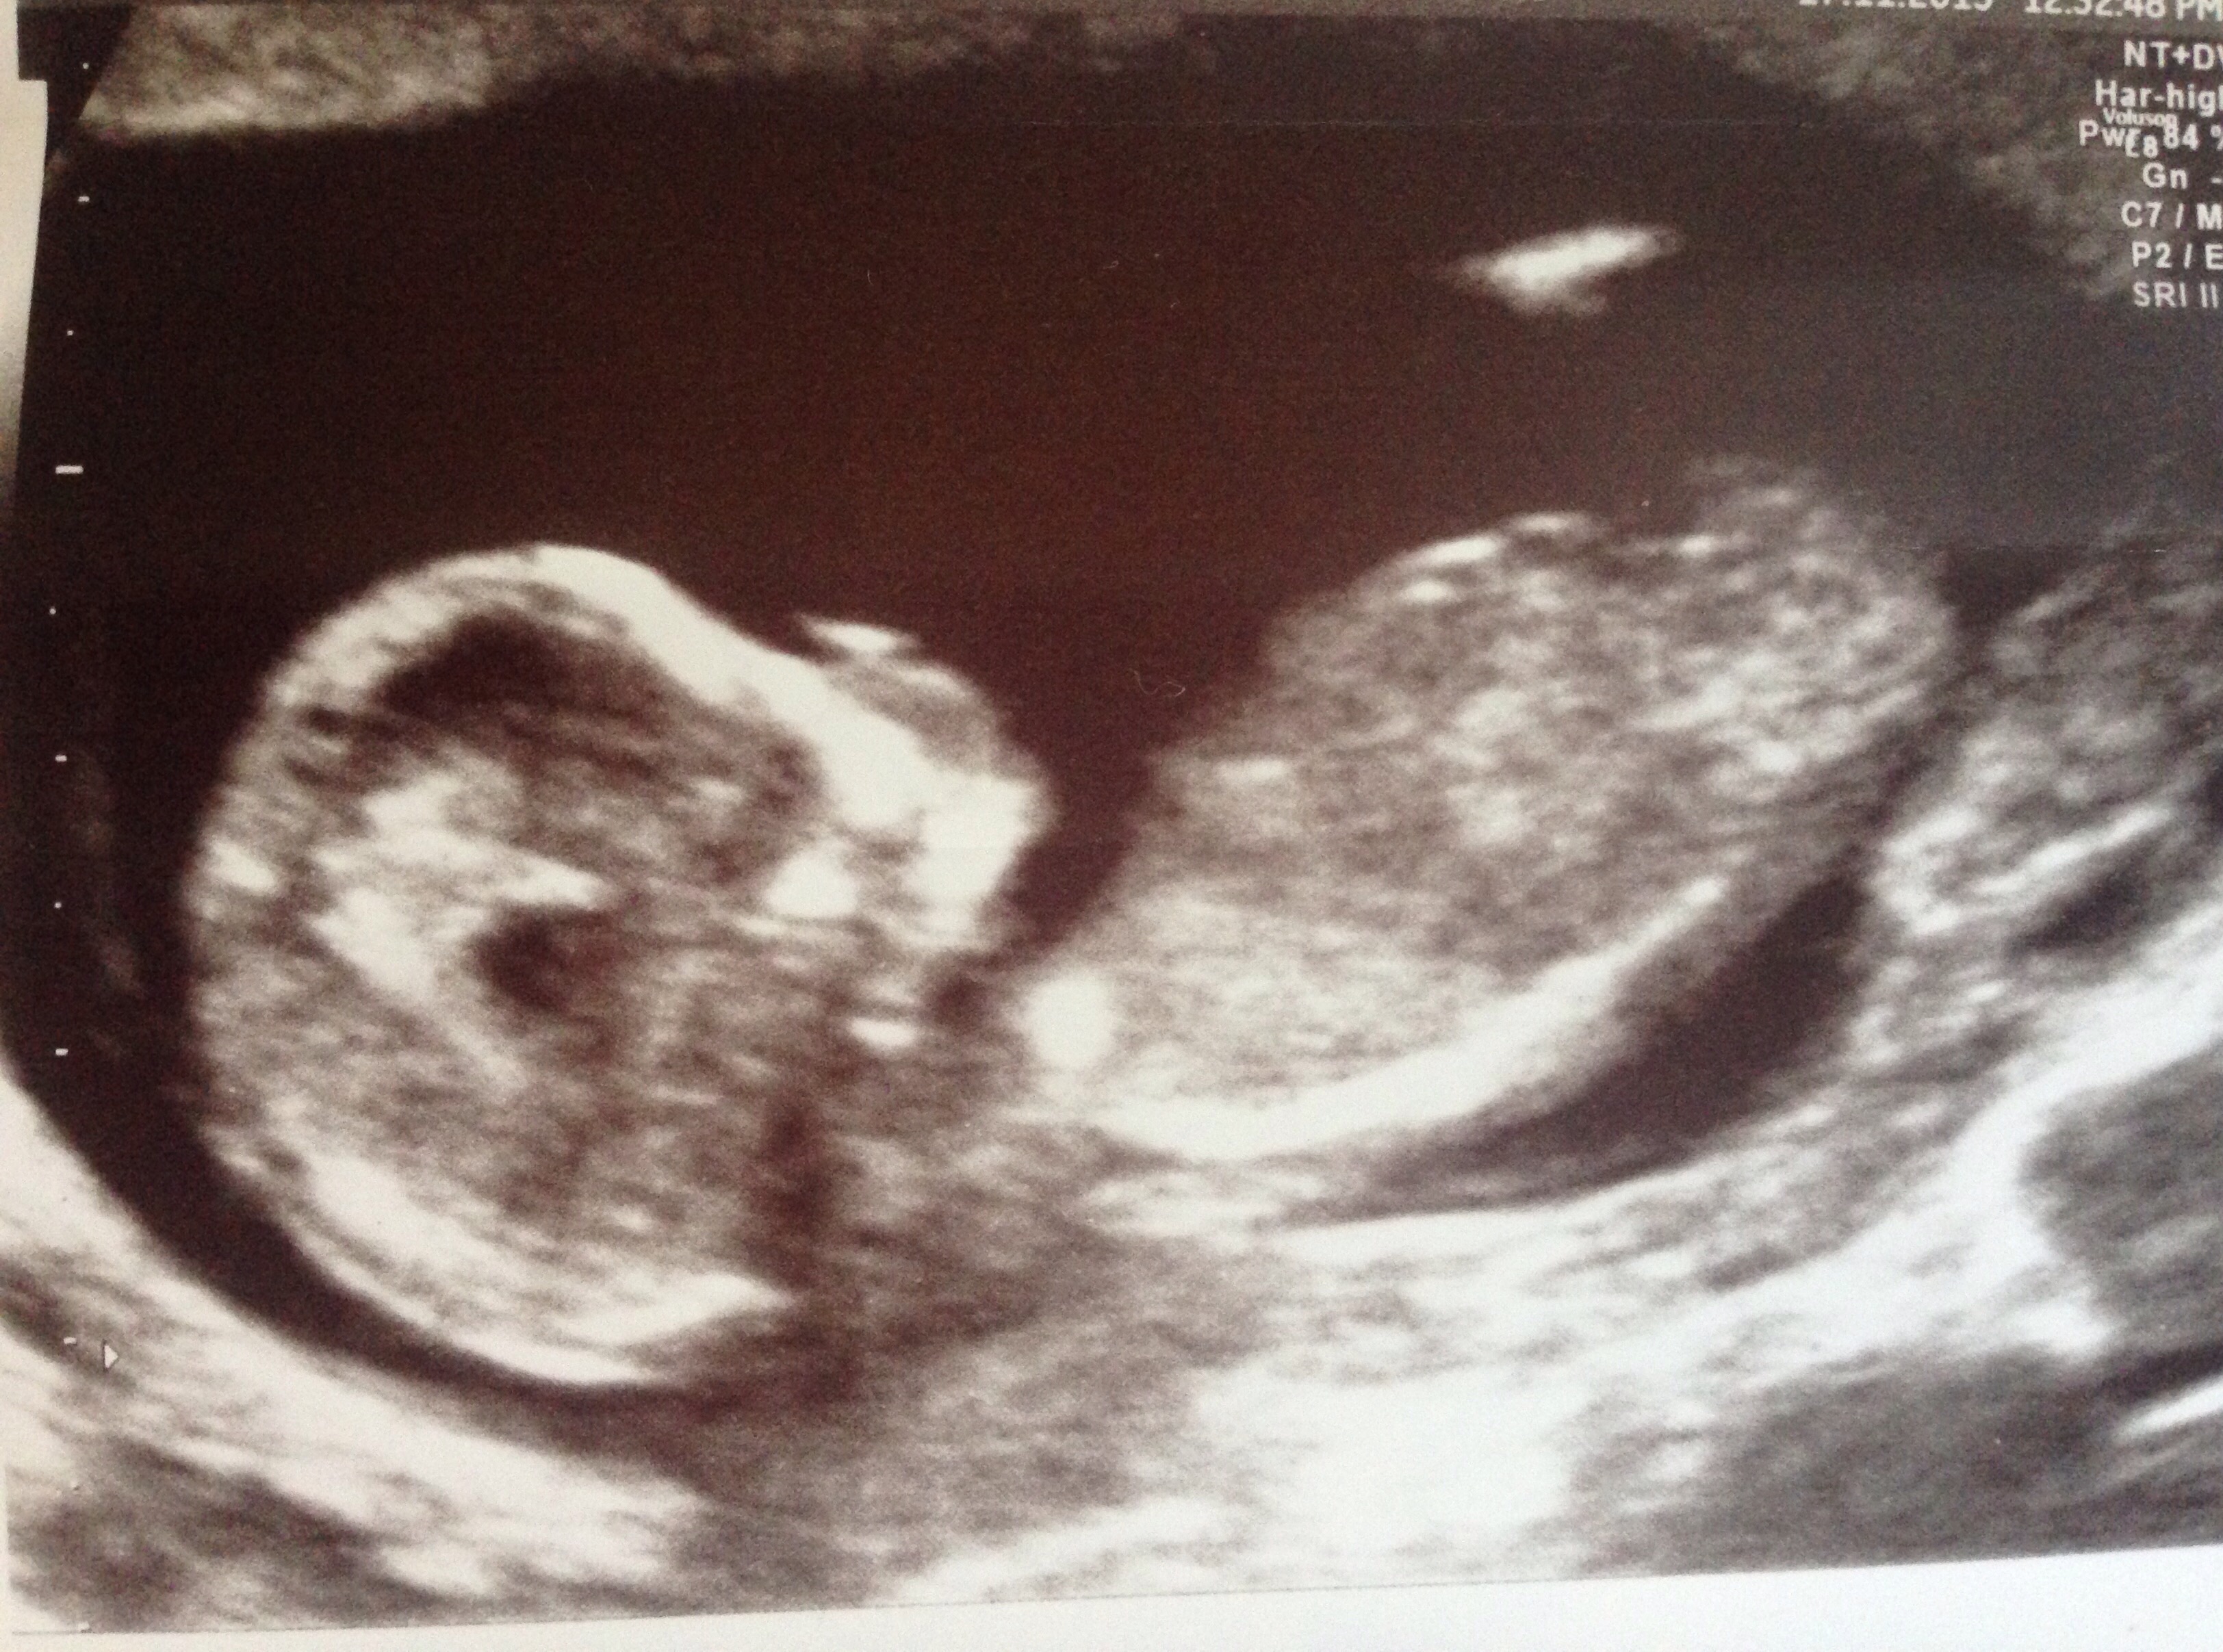

Here are 2 more picturesAttachment 28821Attachment 28822

maybe girl on your second pic.

I would say boy based on secon pic. If that's the nub I think I'm seeing.

It's a GIRL!!!!